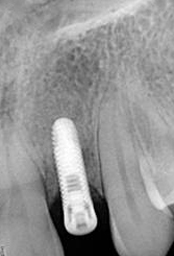

Single Tooth Implant

X-ray of Implant